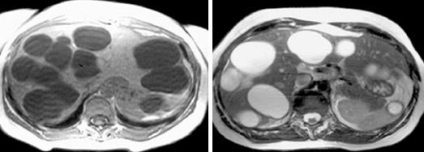

Egy egyszerű ciszta máj

Több máj- hydatid cisztákat és ciszta egység a lépben